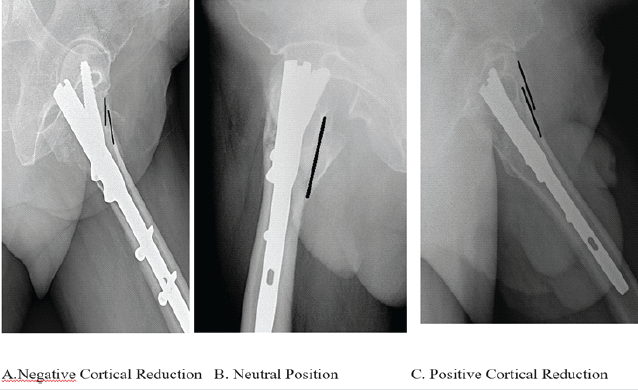

During the immediate post-fixation period (C-arm fluoroscopic imaging) and at subsequent follow-up – 6 weeks, 3 months, and 6 months – standard anteroposterior (AP) radiographs of the hip were obtained. These images were captured with both legs positioned in 15° of internal rotation. Lateral radiographs were also taken with the contralateral hip flexed and abducted to optimize visualization. The quality of cortical reduction was evaluated in the immediate post-fixation fluoroscopic images in both AP and lateral views. In the AP view, it was classified based on the position of the medial cortex between the femoral head–neck fragment and the shaft:

- Positive cortical reduction (PCR): The medial cortex of the proximal head–neck fragment is positioned 1–2 mm medial to the medial cortex of the distal femoral shaft.

- Neutral position (NP): The medial cortices of the head–neck fragment and shaft are anatomically aligned.

- Negative cortical reduction (NCR): The medial cortex of the head–neck fragment is displaced 1–2 mm or more laterally to the medial cortex of the femoral shaft (Fig. 1).

Figure 1: Cortical reductions seen in anteroposterior views of the hip joint.